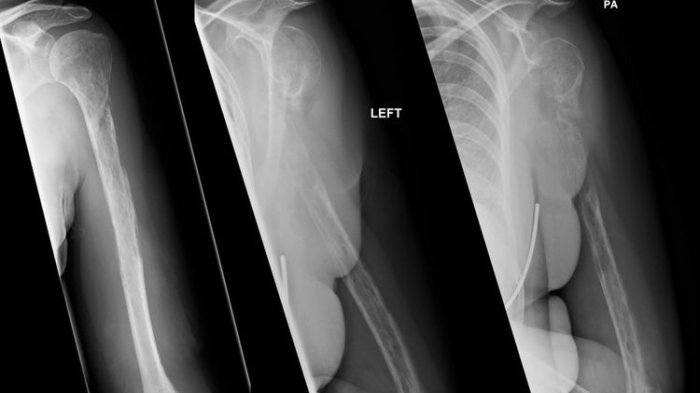

TRIBUNMANADO.CO.ID -Sebuah penelitian yang dipublikasikan di Journal of Bone and Mineral Research Para peneliti mengamati apa yang terjadi pada lemak sumsum tulang dan kesehatan tulang secara keseluruhan ketika terjadi pembatasan asupan kalori.

Penelitian lainnya yang dilakukan pada 2019 mengungkapkan, diet dengan mengonsumsi kalori hanya 30 persen, setara dengan 1.400 kalori per hari untuk lalu dikombinasikan dengan olahraga, dapat menyebabkan hilangnya kepadatan tulang.

Peningkatan lemak pada tulang bagi mamalia, termasuk manusia, dianggap berbahaya karena membuat tulang menjadi lebih lemah.

Lemak yang lebih sedikit pada tulang biasa dianggap sebagai indikasi kesehatan tulang yang lebih baik.

Dari persepektif manusia, diet rendah kalori meski bernutrisi baik dapat memiliki efek negatif pada kesehatan tulang, terutama ketika dipasangkan dengan olahraga.